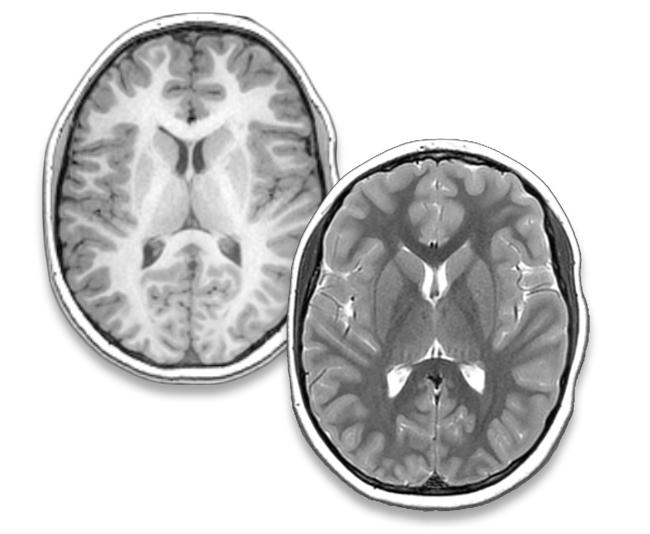

Anatomy

High-resolution anatomical imaging tells us quite a bit about the size and location of lesions after stroke but it also gives much richer information. We can use anatomical scans to measure cortical volumes, thickness of grey matter as well as volumes of subcortical structures such as the thalamus and basal ganglia. Volumes of these structures are highly related to motor function which gives us imaging biomarkers that can subsequently be used for individualized rehabilitation planning.

Often, areas spatially remote from the primary stroke lesion are affected by degeneration via their anatomical connections (diaschisis), a phenomenon that we have measured in the thalamus, cerebellum, corpus callosum and other subcortical areas. We can also combine different types of anatomical images to map the degree of myelination (or lack thereof) across the brain.